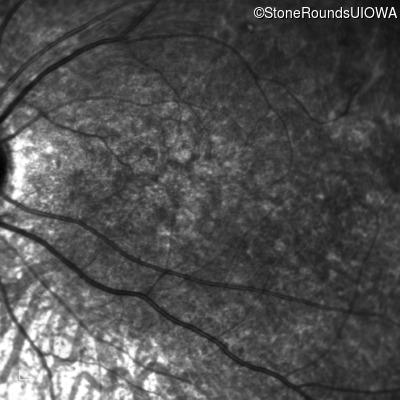

Infrared Fundus Photograph - Left - 5/180

Exemplar